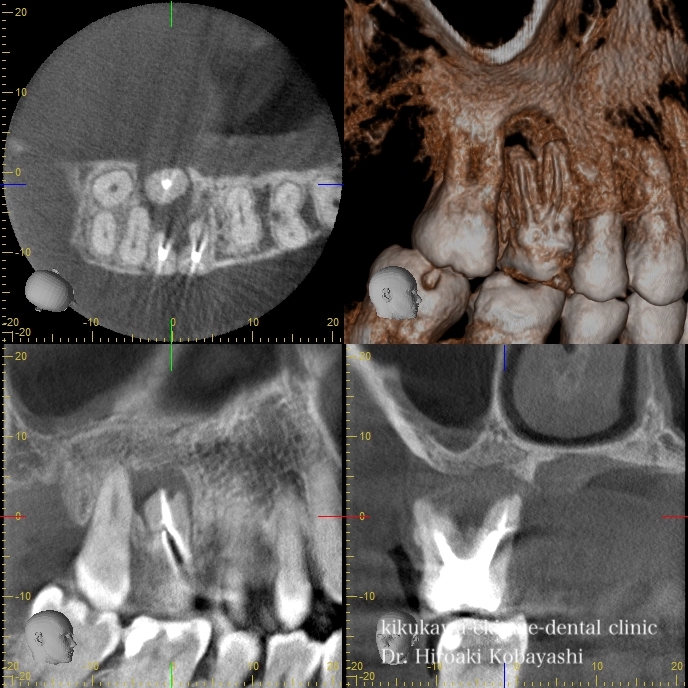

歯茎からオデキが出来たと来院されました。 CT撮影を行いますと、根の感染が見られました。感染の長期の放置により骨が溶けており、歯の保存が難しそうな状況でした。痛みもなく、特に生活に支障はありませんが、刻一刻と早期に歯を失う方向に進んでいます。おそらく、数年このままですと痛みもなくある日、ぐらぐらし、抜け落ちていたでしょう お話し合いの上、精密根管治療にて歯の保存を希望されましたので、治療を開始しました。   時間をかけ、顕微鏡を使用し感染の除去を行なっていきます。過去に根の処置を行なった時に入れたであろう薬剤や膿や出血が出てきます。 2時間程度のアポイントを3回お取りし、精密根管治療が完了しました。 オデキはなくなり、無事歯を残す事が出来ました。   CTにて経過を見ますと骨の再生が起きています 約6ヶ月〜程度かけて骨の再生が起こります。 リスク 極端に硬いものを噛むとかける可能性があります。 各種治療費はこちらから